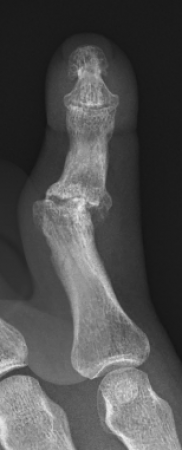

Common symptoms cause pain, and stiffness in the small joints of the hand. The knuckles can become swollen or show bumps and bony nodules called Heberden’s or Bouchard’s nodes in the fingers. Base of thumb arthritis can sometimes lead to the thumb being drawn into the palm and loss of a wide hand span. People often complain of difficulty opening jars and taps. X-Rays are often the most simple and effective way of showing arthritis.

This is the technique of fusing the joint in a position of best function that is appropriate to each individual patient. This is a very durable and reliable way of relieving pain and correcting severe deformity although it does prevent any movement of the affected joint from the fused position. It has been a technique employed since the early 1900’s with good long term results. It is particularly useful in younger patients with a requirement for heavy manual activity and commonly used to treat arthritis in the smaller joints of the fingers such as the DIP joints but can be performed in almost any joint. Risks of surgery include a failure to fuse the joint causing ongoing pain, risk of implant breakage or irritation to surrounding tissues, injury to surrounding structures including skin, nerves, blood vessels and cells that produce the nail and can also be complicated by infection.